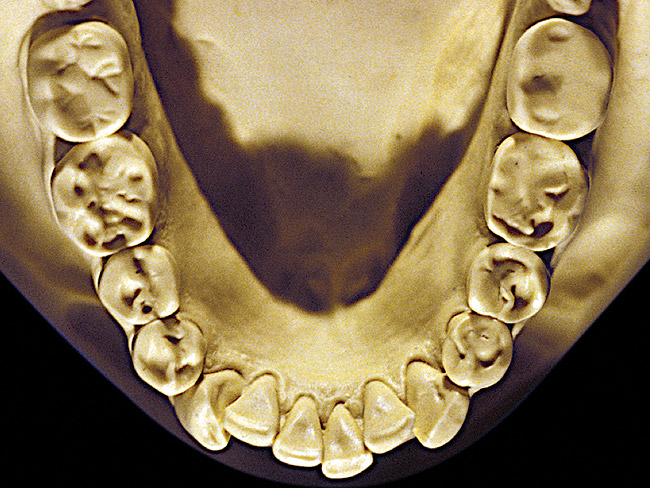

Figure 8  Moderate NCLTS from toothpaste, mandibular arch.

Figure 8

The patient shown in Figure 3 and Figure 4 exhibited severe NCLTS from bruxism. Examination of the casts indicated that the NCLTS was progressively greater toward the anterior teeth. Cupping and cratering was not present because there was no secondary cause. Figure 5 and Figure 6 detail another bruxism patient, but to a lesser degree and one with cupping/cratering caused by toothpaste. The cups or craters were not caused from bruxism because the teeth could not touch the bottom of the invaginations. In both featured patients, upon hand-articulating the casts, the NCLTS facets matched up and the diagnosis of bruxism was confirmed.

Figure 7 and Figure 8 are examples of NCLTS resulting from toothpaste. Upon examination, one could see that the overall anatomical detail of the teeth was faded with a sandblasted appearance. A closer view of the facial surfaces (Figure 9 and Figure 10) illustrates this to a greater degree and one can observe that the normal intricate facial anatomy was completely missing. It is interesting to note there was no cervical recession of the gingiva, even though every surface of every tooth had been abraded. This is due to the fact that this patient had always used a soft, round-ended filament toothbrush.21-22 This patient's sole desire regarding her oral hygiene was to get her teeth whiter.

So that the previous example is not misleading, the behavioral profile of the toothpaste abuser is not necessarily the "caries-free immaculate oral hygiene patient," but can be virtually anyone who brushes their teeth with toothpaste. Figure 11 and Figure 12 illustrate a more advanced example of toothpaste abuse showing a patient with multiple restorations and some unkempt teeth. The anatomical details were faded with a sandblasted appearance and the silver alloy restorations were highly polished. The facial surfaces of the mandibular canines and premolars were affected the most, creating the pathognomonic pattern. Figure 13 and Figure 14 are a close-up view of this area, illustrating a cupping or cratering effect, but of the asymmetrical variety. This patient did not like the color of his teeth and spent an inordinate amount of time brushing his teeth. Again, likewise due to the exclusive use of a round-ended, soft-bristle toothbrush, note there was no cervical gingival recession in this case either. When the featured casts illustrating toothpaste abuse (Figure 7, Figure 8, Figure 9, Figure 10, Figure 11, Figure 12, Figure 13 and Figure 14) were hand-articulated, the worn surfaces did not match up and the diagnosis of toothpaste abuse was confirmed.